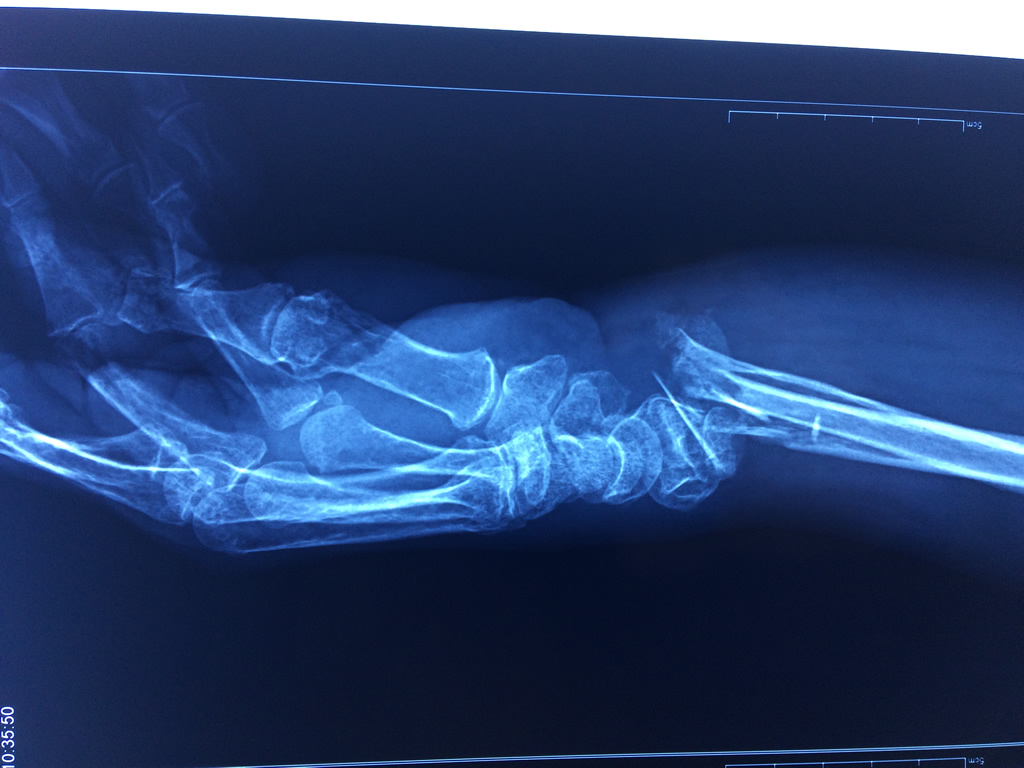

Cirugías de Codo - Cirugías de Muñecas y Manos

Los procedimientos más comunes en cirugía de la mano son aquellos destinados a reparar traumatismos, incluyendo lesiones de tendones, nervios, vasos sanguíneos, y articulaciones; huesos fracturados; y quemaduras, cortes, y otros daños de la piel.